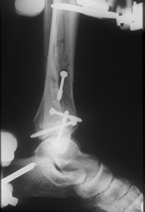

Korrekte Positionder Pins bei gelenküberbrückender Montage

Montage des Hoffmann© II, die schrägverlaufende Carbonstange bringt die entscheidende Stäbilität bei erhaltener Elastizität